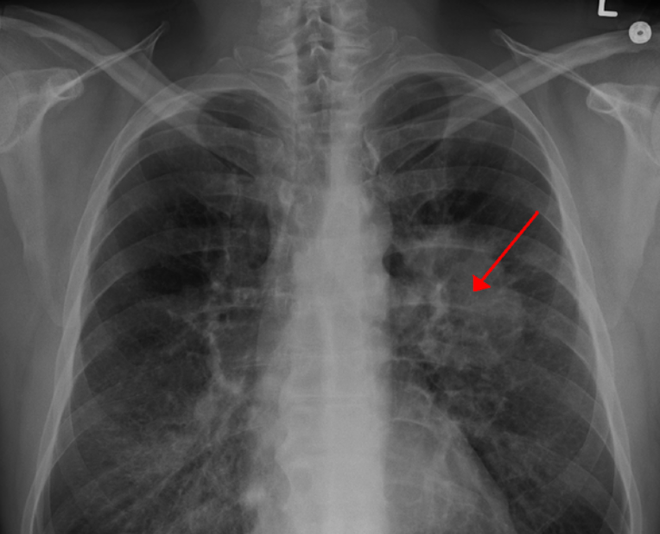

Israel phát triển phương pháp mới chữa trị ung thư ảnh 1Israel phát triển phương pháp mới chữa trị ung thư. (Nguồn: sharylattkisson.com)

Theo phóng viên TTXVN tại Israel, ngày 27/2, bệnh viện Beilinson ở miền Trung Israel cho biết các bác sỹ đã đưa phổi của một bệnh nhân ung thư ra khỏi cơ thể, làm sạch phổi khỏi các khối u và nối lại phổi thành công cho cơ thể của bệnh nhân này.

Cho tới nay, bệnh nhân ung thư trải qua phẫu thuật chịu tổn thương từ khối u, gây ra tình trạng tắc nghẽn di chuyển của không khí trong phổi trái, dẫn đến việc phổi không hoạt động đúng chức năng.